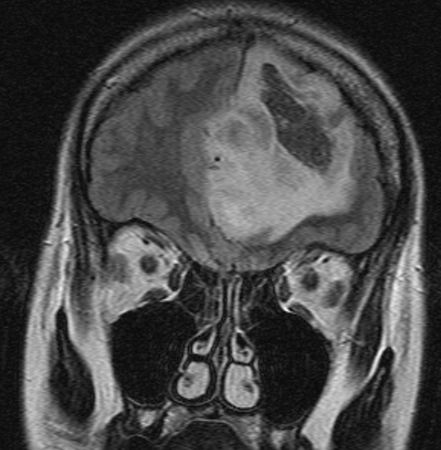

| Astrozytom II | 33jährige Frau mit einem links-frontalen Gliom Grad 2.![]()

![]() | |||||||||||||||||||||||||||||||||||||||||||||||||